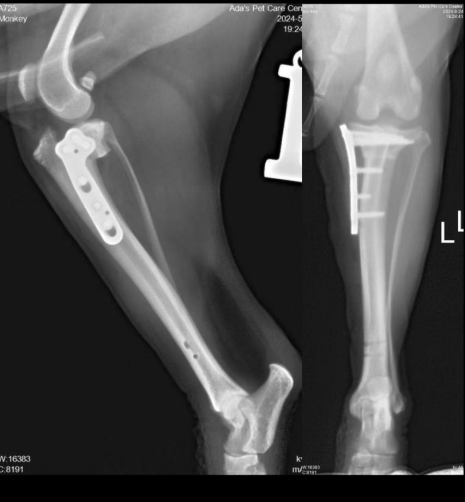

After hearing the diagnosis, the owner was understandably distressed. Dr. Sun provided a detailed explanation of the condition and treatment options. After a period of consideration, the owner decided to proceed with surgical treatment. A TPLO (Tibial Plateau Leveling Osteotomy) surgery was scheduled, and Monkey was admitted to the hospital for the procedure.

After surgery, Monkey’s recovery from anesthesia was smooth, with no signs of vocalizing, rolling, or other pain-related symptoms. About three days post-op, Monkey began to gradually bear weight on his left hind leg while standing. Around seven days post-op, he was able to walk with all four limbs at a slow pace. After about 10 days of hospital rest and recovery, Monkey was discharged and returned home to continue his recovery. He is now full of energy and recovering very well at home.